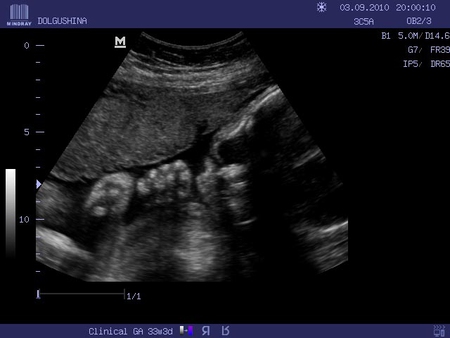

Что бы хорошего написать? Вчера видела свою девочку на УЗИ!

Эх, будет у нас еще одна девчонка! А я так на пацана надеялась. Будет в семье только один мужик - папа, так как на третьего ребенка я не соглашусь ни за что на свете, я уже предупредила родственников, чтобы пристрелили меня, если только заикнуть о третьем. В общем расстроилась я немного, хотя и знаю, что буду любить малышку ничуть не меньше, чем Янку.

Сильно обеспокоило обвитие пуповиной, хотя все и говорят, что это не так уж и страшно.

Лежит головкой вниз (умничка мамина), сердечко бьется с частотой 160 уд/мин.

Окружность головки, 300 мм, животика 282 мм, длина бедра 62 мм, голени 53 мм, плеча 53 мм, предплечья 45 мм.

Размеры плода соответствуют 32-33 неделям. Вес 1954 г.

Внутренние органы в норме, не изменены, позвоночник и носогубный треугольник цел.

Воды в норме, степень зрелости плаценты - 2. Там много еще чего написано, но перечислять все это здесь не имеет смысла.

УЗИ мне очень понравилось, врач все нам показала, рассказала, дала диск с фотками, на них правда, почти ничего не понятно.

Я когда увидела на экране маленькую носопырку, чуть не расплакалась. А вот и мое солнышко: